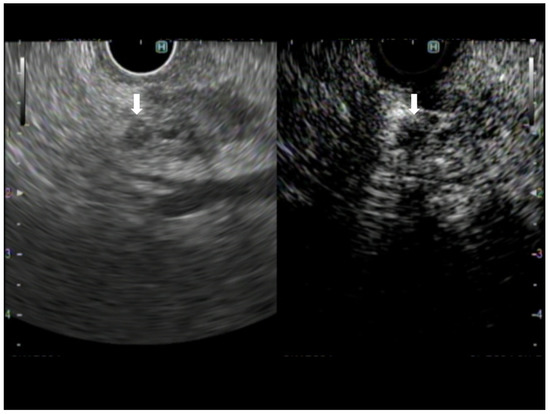

5. Detection of Subtle Lesions

- Sakamoto, H.; Kitano, M.; Suetomi, Y.; Maekawa, K.; Takeyama, Y.; Kudo, M. Utility of Contrast-Enhanced Endoscopic Ultrasonography for Diagnosis of Small Pancreatic Carcinomas. Ultrasound Med. Biol. 2008, 34, 525–532. [Google Scholar] [CrossRef]